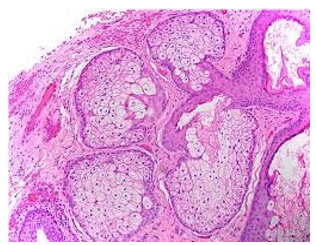

Upon microscopic examination, mature sebaceous glands appear aggregated subjacent to mucosal epithelium. The visible sebaceous glands appear in continuum with superimposed cutaneous surface and are devoid of associated hair follicles [6,7]. Nevertheless, a ductal communication with superficial epidermis may be absent [6,7].

The morphological countenance is akin to normal cutaneous adnexal sebaceous glands. Superimposed stratified squamous epithelium demonstrates parakeratosis and exhibits subjacent lobules of mature sebaceous glands [6,7].

Figure 6: Fordyce's granules delineating several lobulated sebaceous glands with lipid-rich cells and an enveloping fibrotic stroma (14).